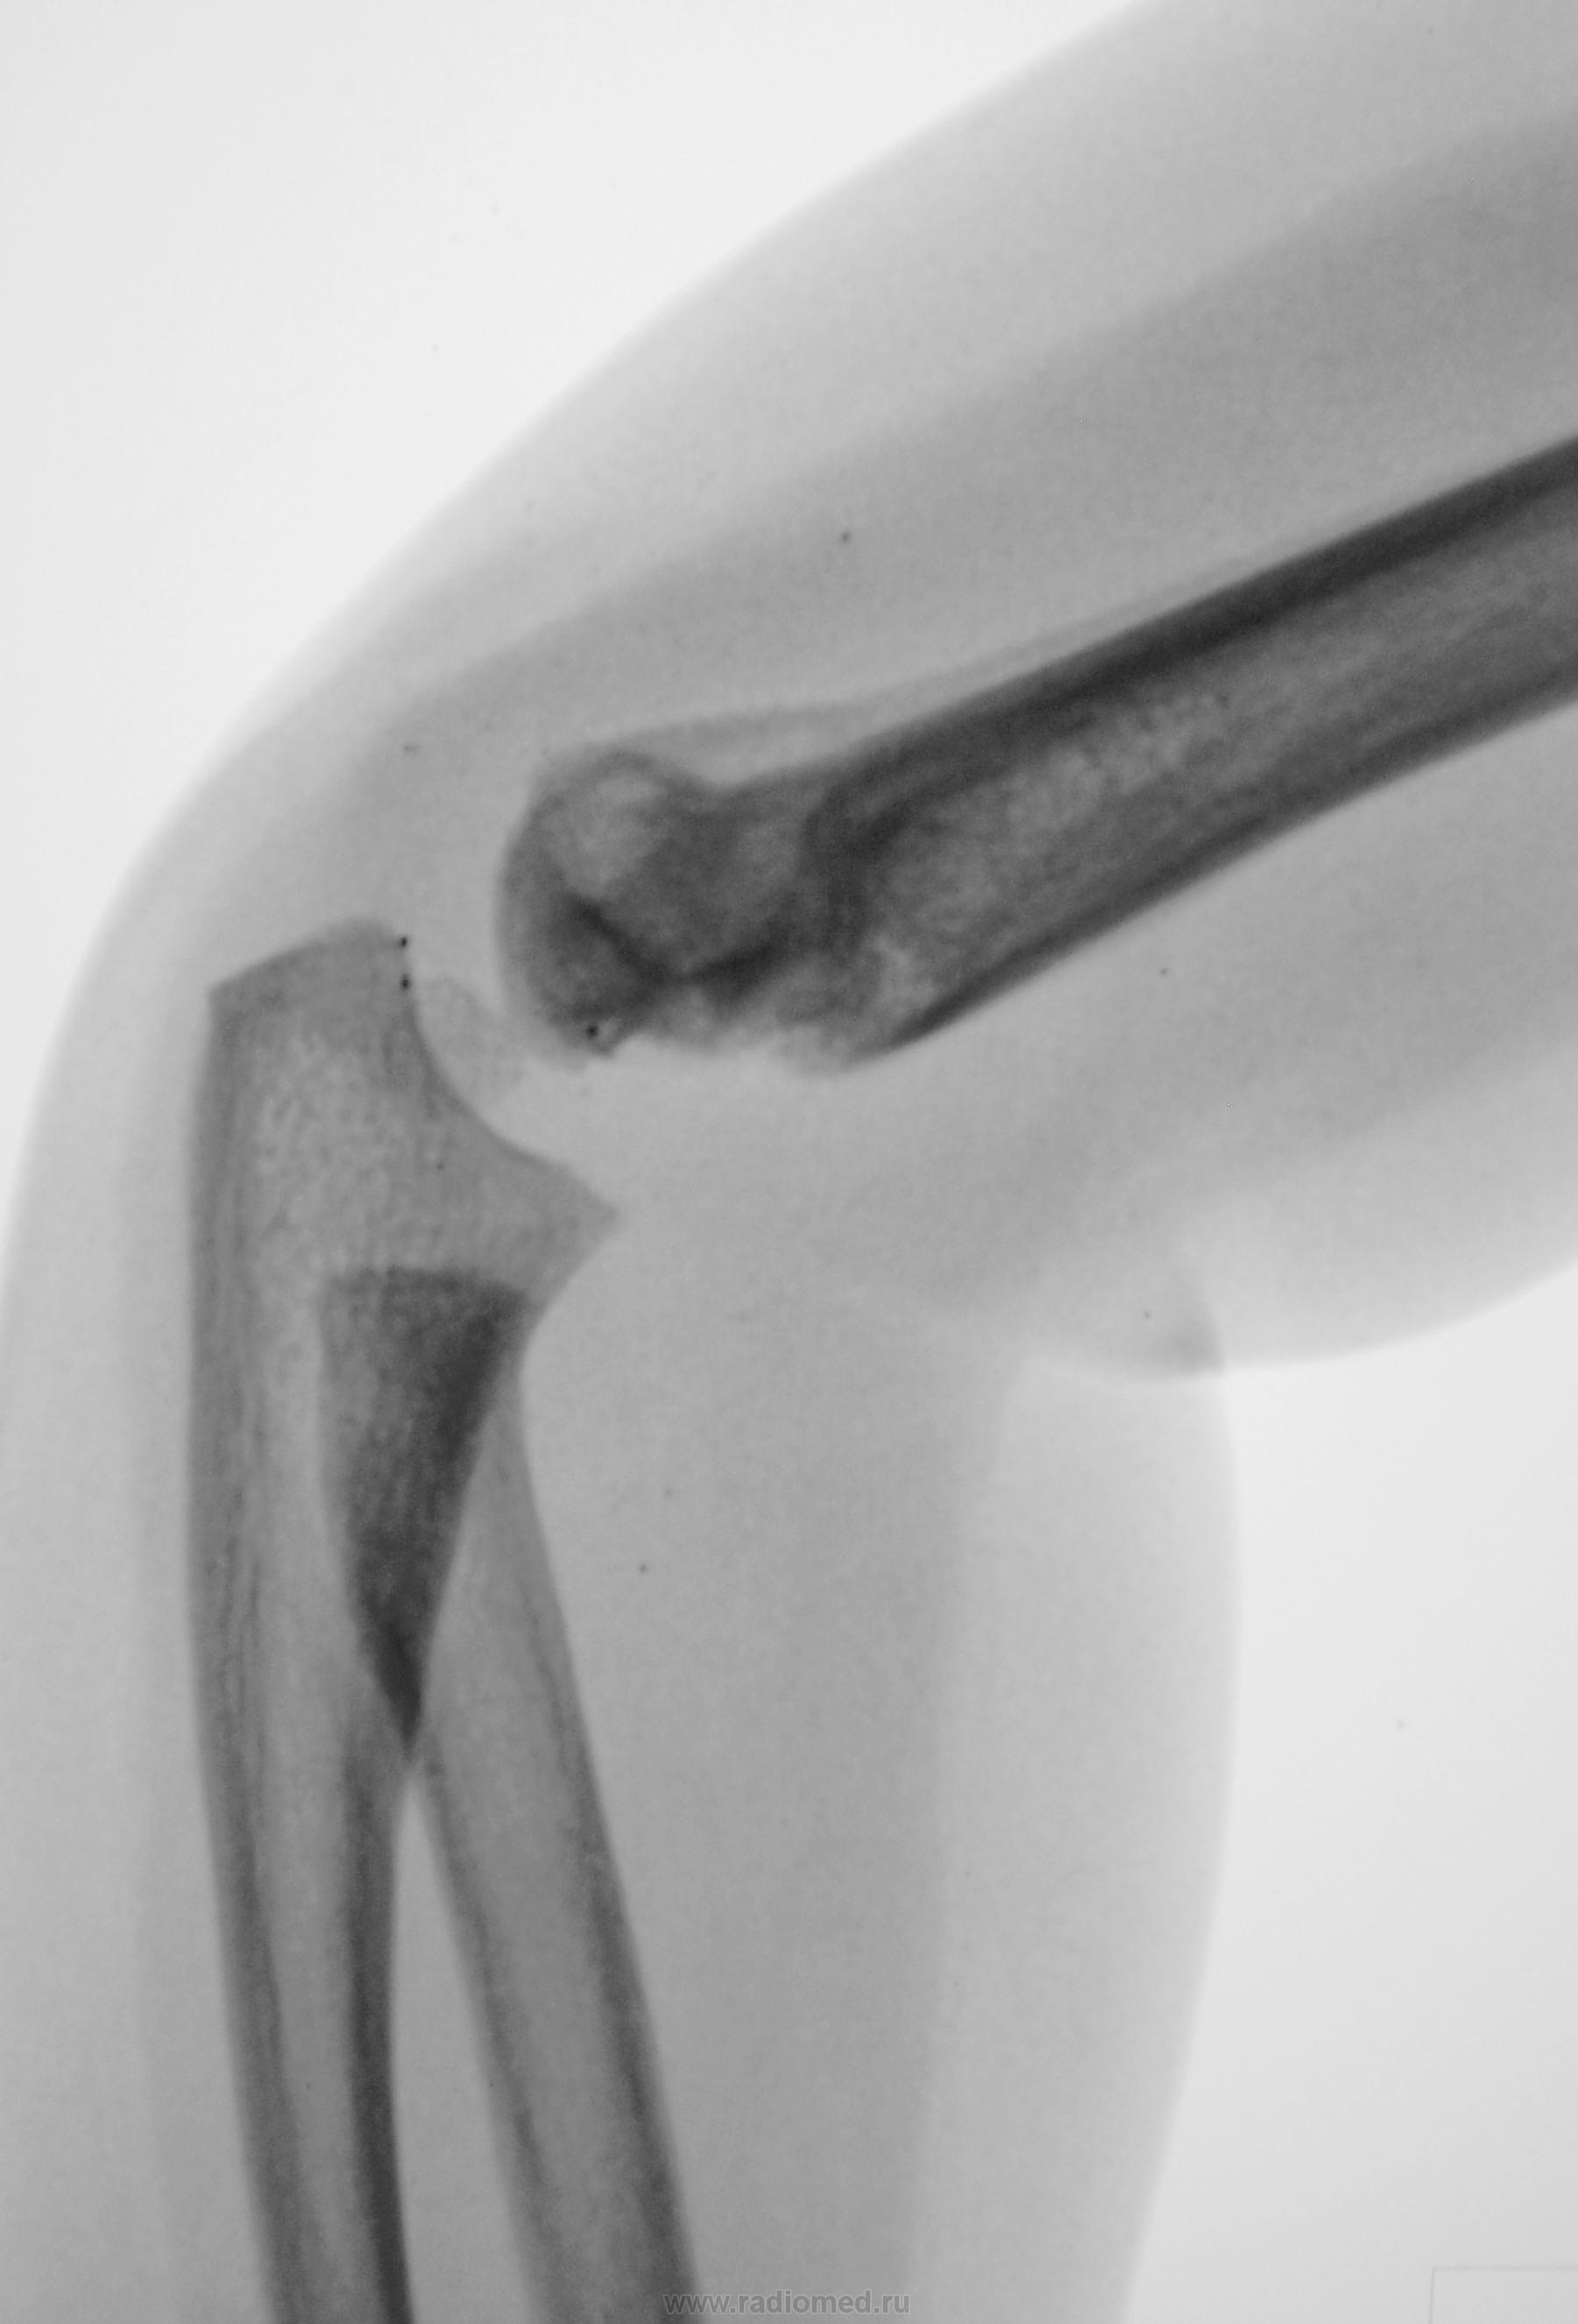

Ребенок. Снят гипс.

Первичный снимок.

3 года.

Консолидирующийся чрезмыщелковый перелом плечевой кости. Есть, конечно, угловое смещение кзади, надо было сразу репонировать, а теперь не знаю, может, для такого возраста можно и оставить.

углок есть, консолидация достаточная для того, чтобы уже начать разрабатывать сустав. Все не так уж и плохо))))

Обычный срастающийся с допустимым смещением чрезмыщелковый перелом. Подвывихов нет.